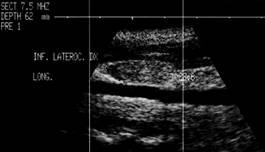

Loja laterocervicala dreapta.

Loja laterocervicala stanga

Femeie 31 ani. Leziuni hipoecogene, neomogene laterocervical bilateral. Tiroidectomie totala pentru neoplasm papilar cu extensie extracapsulara si metastaze linfonodale (T4 N1 M0) in urma cu 2 ani. Terapia radiometabolica.

Examen citologic: celule epiteliale gigante ca in granulomul

de corp strain; fibroza cronica granulomatoasa supurativa. Tireoglobulina din lichidul

de lavaj: nedozabil.

Aceeasi pacienta – fara semnal de vascularizatie

interna.